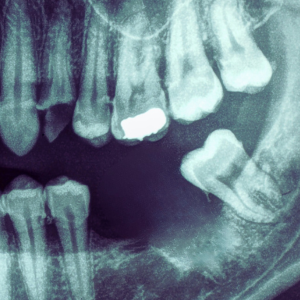

Our practice uses advanced 3D imaging, facial scanning, and digital surgical planning to design a custom guide for your implant placement. This technology ensures every implant is positioned with micron-level accuracy, leading to a perfect fit and faster healing.

With thousands of implants placed, our skilled surgical team combines digital precision with human expertise—delivering results that look, feel, and function naturally. Our fully digital process is faster, more flexible, and entirely customized to you.